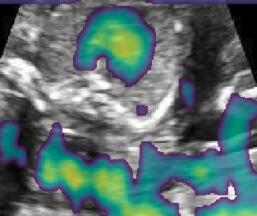

Fig. 9 qualitatively shows that shadow confidence maps are able to improve the performance of US image fusion algorithms with different weighting strategies. Fig. 9 also shows the difference between adding two different types of confidence maps. These two types of confidence maps are generated by the confidence estimation network which are separately trained by either MSE or Sigmoid loss. Fig. 9 (a) to (d) illustrate image fusion results for the same case using different combinations of weighting strategies and loss functions. The difference maps indicate that shadow confidence maps are capable of improving image fusion performance. Fig. 9 (e) to (h) show image fusion results on four different cases. We randomly select two positively affected cases (Fig. 9 (e) and (f)) to show visual improvement. We additionally show two randomly selected examples (Fig. 9 (g) and (h)) that don’t show perceptually significant improvements after adding shadow confidence maps. Quantitative evaluation for image fusion is not possible because of lacking a ground truth for US compounding tasks.

-G Examples for Image Fusion

Fig.15 shows more examples of the multi-view image fusion task which include the original multi-view images. From the column (a-b) of Fig.15, we can see that the original images contain strong shadow artifacts that can affect the anatomical analysis. The image fusion task aims to use complementary information from images with different views for reducing artifacts and increasing anatomical information. Column (e-f) enlarge the areas within the bounding boxes in column (c-d). Column (g) shows the difference masks between column (e)and (f). The difference masks clearly indicates the improved performance of image fusion after adding shadow confidence maps for Gaussian weighting strategy as well as Intensity and Gaussian weighting strategy.